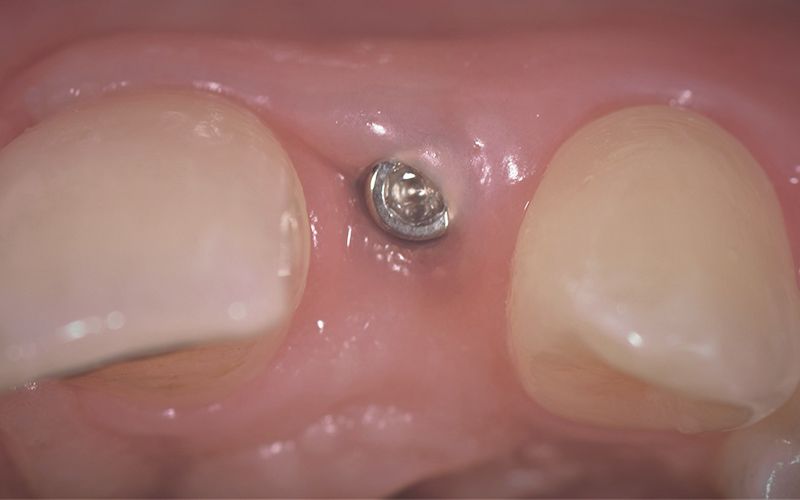

Tras tres meses de osteointegración, se procedió a realizar la segunda cirugía de ambos implantes y se tomaron las impresiones digitales con el escáner intraoral TRIOS (3Shape).

Se mandaron las impresiones a un laboratorio protésicos de confianza para la confección de unos provisionales mientras trabajaban en el diseño y confección CAD-CAM de las coronas definitivas de zirconio.

Las coronas de zirconio monolítico fresado con cut-back iban cementadas sobre dos bases de titanio previamente talladas para salvar el eje de inserción de los implantes.

Al cabo de unos días se hicieron los controles clínicos y radiológicos pertinentes y se procedió a cementar las dos coronas de forma definitiva dando por finalizada la rehabilitación por agenesia de los dos incisivos laterales 12 y 22.